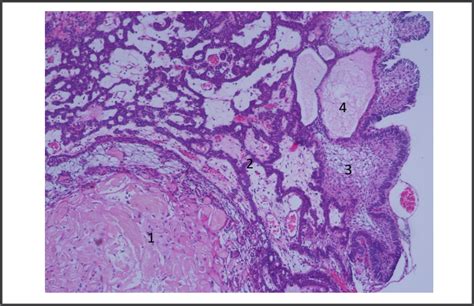

Craneofaringioma, also known as craniopharyngioma, is a benign tumor that develops near the pituitary gland at the base of the brain. Despite being benign, these tumors can cause significant health issues due to their location and potential to compress nearby structures. The tumor can affect various bodily functions, including vision, hormone regulation, and brain function.